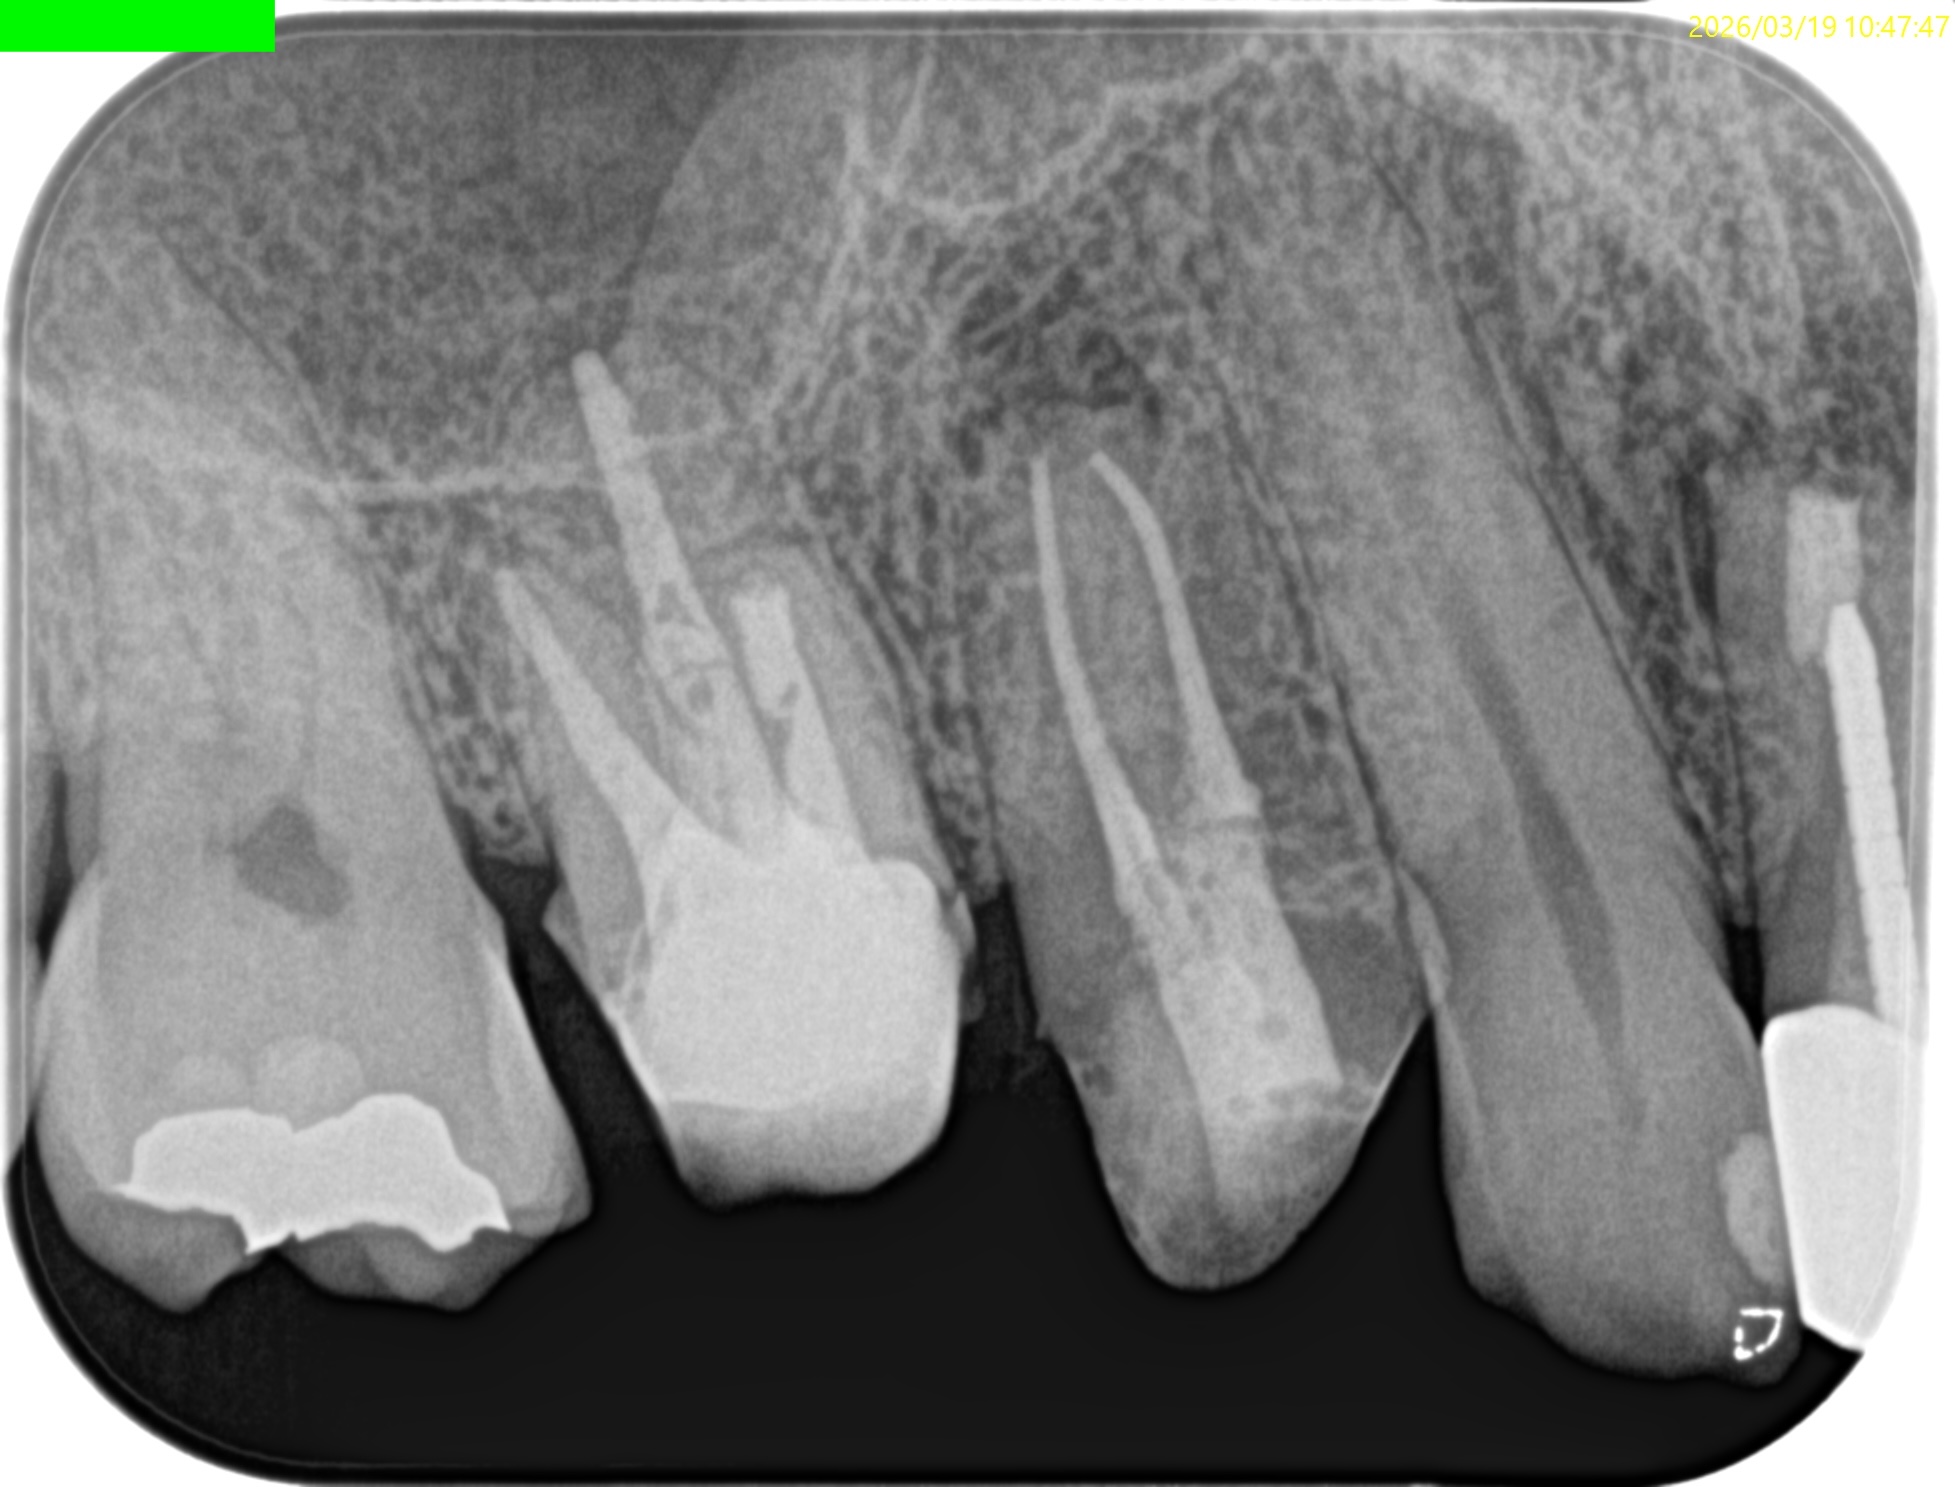

#3 MB Apicoectomy 1yr recall(2026.3.19)

歯槽骨の欠損、Sinus tract, 臨床症状は消失した。

最終補綴もOKで、経過観察も終診とさせていただいた。